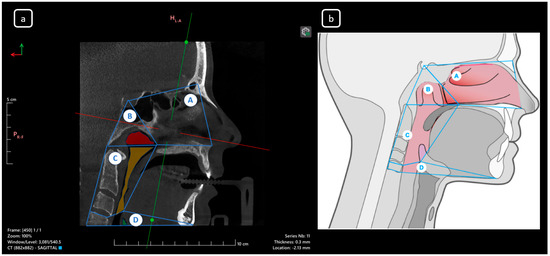

Cone beam computed tomography (CBCT) is a valuable diagnostic tool for evaluating the upper airway and maxillofacial region. This report demonstrates the clinical value of CBCT in identifying significant anatomical variations in endodontics, incidentally detected on a non-endodontic CBCT scan. A 23-year-old female patient underwent CBCT imaging at the Faculty of Dentistry-UJED to evaluate her upper airway. CBCT imaging revealed a unique, complex, and unusual anatomy of mandibular root canals, characterized by Vertucci’s type III root canals in the anterior sextant and co-occurrence of bilateral C-shaped mandibular second molars (type C2 according to Fan’s classification). No therapeutic interventions were initiated due to the patient’s asymptomatic status. CBCT imaging is a valuable tool for integrated diagnostic approaches, underscoring its role in thorough patient management. The integration of multidisciplinary interpretation of CBCT data can enhance diagnostic accuracy and optimize patient records and management, emphasizing the importance of collaborative efforts between radiologists, clinicians, and endodontists. Documenting and sharing such findings can increase awareness of rare anatomical variations, facilitating detection and contributing to medical knowledge. Full article

Figure 1